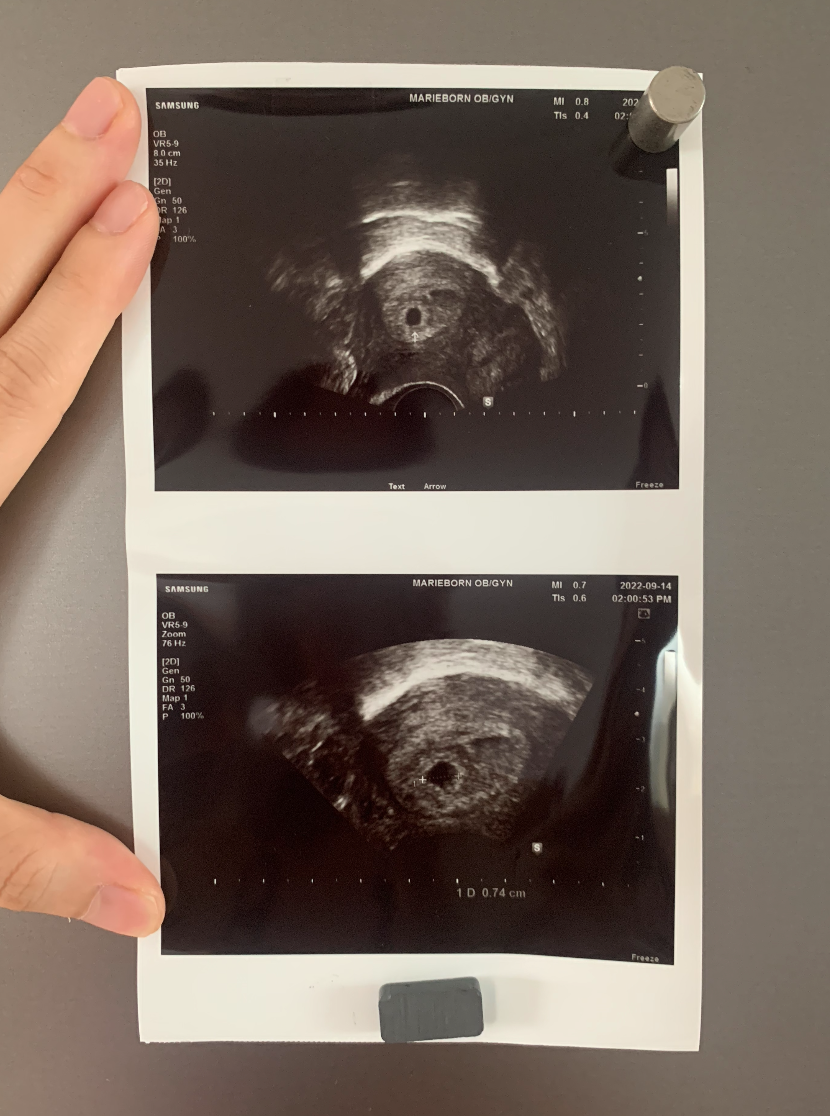

임신을 확인한 지 며칠 차.